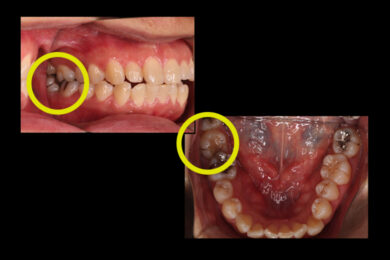

親知らずの前にある奥歯が斜めに生え、年々倒れていくのが心配になり来院されたケースです。

倒れた歯は歯磨きがしにくいため虫歯になっていました。

①倒れている歯の後ろにある親知らずは虫歯になっており、咬み合う歯がないため抜歯しました。

③歯がまっすぐに起き上がったら、ワイヤーによる部分矯正でさらに微調整をします。手前の歯と繋げて位置を調整したら保定期間を設けます。